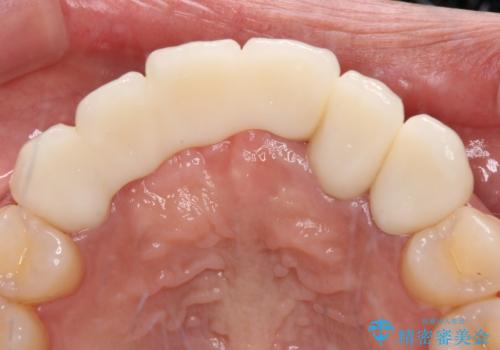

1回の歯肉移植により歯肉の厚みは大幅に改善されましたが、折角なのでもう少し大きくしたいとの要望があり、2回目の処置も行うこととしました。

厚みも高さも十分な歯肉量を獲得することができました。